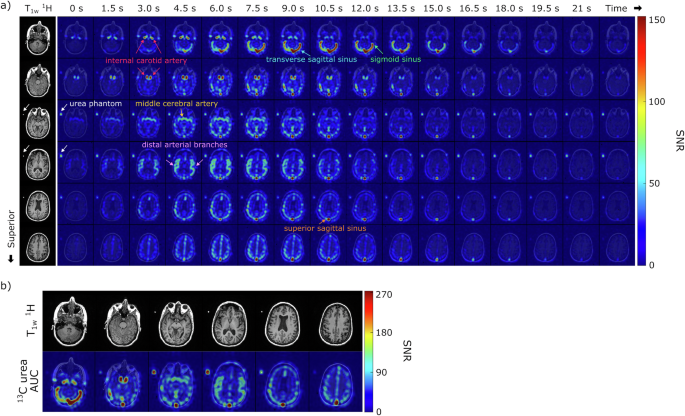

The time course of HP [13C,15N2]urea signals from healthy brain volunteers is illustrated in Fig. 2a and Supporting Information Figs. S2 and S3. The spatial resolution achieved was 7.76 × 7.76 × 15 mm3, comparable to the highest reported resolution of HP [1-13C]pyruvate acquisition (7.5 × 7.5 × 15 mm3)34. Urea images clearly delineated the cerebrovascular system, including the anterior circulation (internal carotid and middle cerebral arteries), posterior circulation (vertebral and basilar arteries), and dural venous sinuses (transverse/superior sagittal sinus, sigmoid sinus). These images captured dynamic signal intensity changes corresponding to the in-flow and washout of HP [13C,15N2]urea compounded with T1 relaxations of HP magnetization.

a Corresponding 1H anatomical images and the dynamic HP [13C,15N2]urea images (7.76 × 7.76 × 15 mm3) overlaid on the 1H anatomical images are displayed. A total of 20 slices and 32 timeframes were acquired, and this figure displays the middle 6 slices and the first 16 timeframes (1.5 s temporal resolution). White arrows indicate the signal from the urea phantom. b Total signal (area-under-curve, AUC) images of urea from the same subject. The urea images overlaid on the corresponding 1H anatomical images are shown.

Initially, the urea bolus signal appeared in the internal carotid and middle cerebral arteries, followed by the distal arterial branches, and eventually in the venous system, specifically well seen in the transverse and sagittal sinuses (Fig. 2a). Asymmetric flow of urea into the left and right transverse sinuses was observed in most volunteer datasets, consistent with normal anatomic variation35. The peak dynamic SNR in this dataset was 380, observed within the confluence of sinuses at the 8th timepoint (10.5 s after the saline injection ended). An average peak SNR of 253 ± 136 was measured in the superior sagittal sinus across all volunteer datasets (n = 8) with one exception where the peak signal was observed in the superficial temporal artery. Area-under-curve (AUC) images from a representative subject, shown in Fig. 2b, highlighted signals from the blood vessels, but no urea signal was observed in the brain parenchyma, consistent with urea not crossing the blood–brain barrier (BBB).